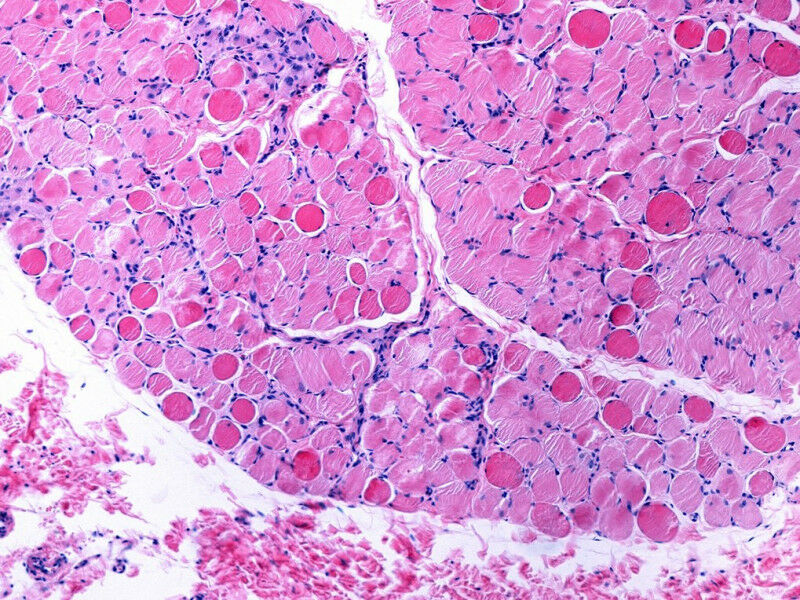

Bei der Duchenne Muskeldystrophie (DMD) handelt es sich um eine seltene Erbkrankheit, die mit zunehmendem Muskelschwund einhergeht. Die Erkrankung verläuft chronisch und beginnt bereits im Kindesalter. Die Lebenserwartung bei den betroffenen Patienten ist deutlich verkürzt. Verursacht wird die bislang nicht heilbare Erkrankung durch Mutationen im Dystrophin-Gen. Dieses liegt auf dem X-Chromosom. Dystrophin ist für die Stabilität der Zellmembran in Muskelfasern wichtig. Durch den Gendefekt fehlt Dystrophin, so dass die Muskelzellen in ihrer Funktion eingeschränkt sind und die Muskulatur zunehmend geschwächt wird.